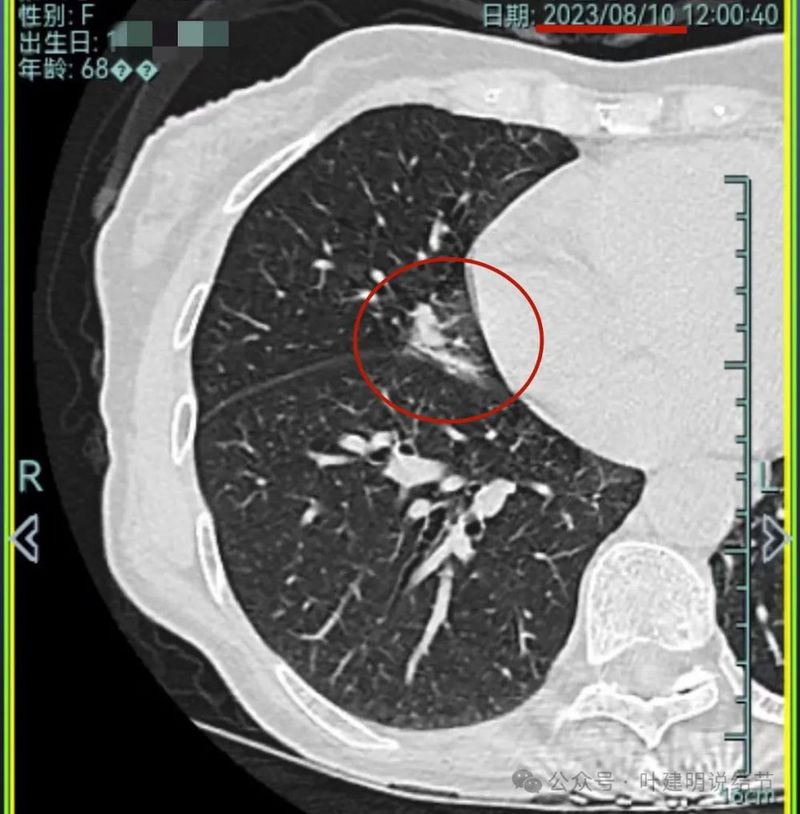

再看2023年8月的影像:

病灶4 仍是钙化的,大小也没有进展。

病灶5较前密度又有增高,贴着叶间裂,整体轮廓显得较之前清楚些,更符合恶性表现了,而且应该是浸润性腺癌。

我想我们这样也来考虑问题:1、左侧已经手术的确诊是肿瘤性质,左上已经消融的也是随访持续存在的磨玻璃密度结节,虽然没有病理依据,仍然要考虑广义上来讲的肿瘤范畴,看了以前的片子,从2019年到2023年并没有显著的进展,大概是肺泡上皮不典型增生可能性大。右侧的也有磨玻璃结节与混合磨玻璃结节考虑是肿瘤范畴的。所以总体上两肺多原发早期以磨玻璃为表现的肺癌,整体风险都不大。2019年切除的左肺下叶病灶也是纯磨玻璃密度,其实如果继续随访或者只做楔形切除也并没有什么关系。这说明体质本身或者致病的因素,就是容易长磨玻璃肺癌的,即便把目前发现的都解决,后续仍可能再有新的。原因不明,致病因素仍在。2、右肺上叶红色之处从2019年开始,是逐渐进展的,当然即便是现在,也不是说危险就已经很大,考虑仍然是原位癌或者微浸润性腺癌可能性大;中叶蓝色这处乍一看像至少是微浸润,但前后对比以后发现从2019年到现在,几乎没有显著进展,这样的话慢性炎伴肺泡上皮增生或者伴纤维增生也是有可能的,至少风险并不能认为大;右肺下叶黄色这一处,使纯磨玻璃密度,整体轮廓与边界清楚,考虑是肿瘤范畴的,不典型增生可能性较大,也有可能原位癌,随访稍有进展,风险仍然不大;中叶绿色这处是慢性炎伴钙化的,靠近叶裂的地方也像慢性炎,但此处随访有所进展。不过因为有卫星灶,整体显得比较散,所以虽然恶性可能性较大,但也不能完全除外炎性的可能性。当然如果此灶确实恶性,那风险则相对较其他进展缓慢的要高一些。从目前右侧所在的这些病灶来讲,真正有一定的风险而且最为确切的是红色这处,而且应该也没有到浸润性腺癌或者说不处理会要转移很危险这种程度。3、明确了多原发早期肺癌没有办法预防与控制,也明白了目前已经存在的较明显的这些病灶总体风险的高低。我们再来考虑需不需要近期干预处理。左侧既手术过又消融过,右侧的多发病灶目前又还没有到危险很高的程度,又没有办法预防后续再有新的病灶。我个人偏保守,我觉得仍然可以半年复查随访,如果最具风险的病灶有进展并且不处理可能导致不良后果,到这样的程度再来考虑综合如何处理干预便可。4、假如右侧我们予以处理,上叶红色的以及中叶蓝色的都可以楔切,但绿色考虑良性的再进展或以后像恶性时怎么办?而若中叶切除加上叶楔切,在左侧已经手术过的情况下肺功能影响相对也不小,何况右下比较中间的位置还有桔色这处呢。当然右下这处得考虑消融。所以,我的想法还是能熬再熬下,待其他监测有变化再通盘考虑。意见供参考!